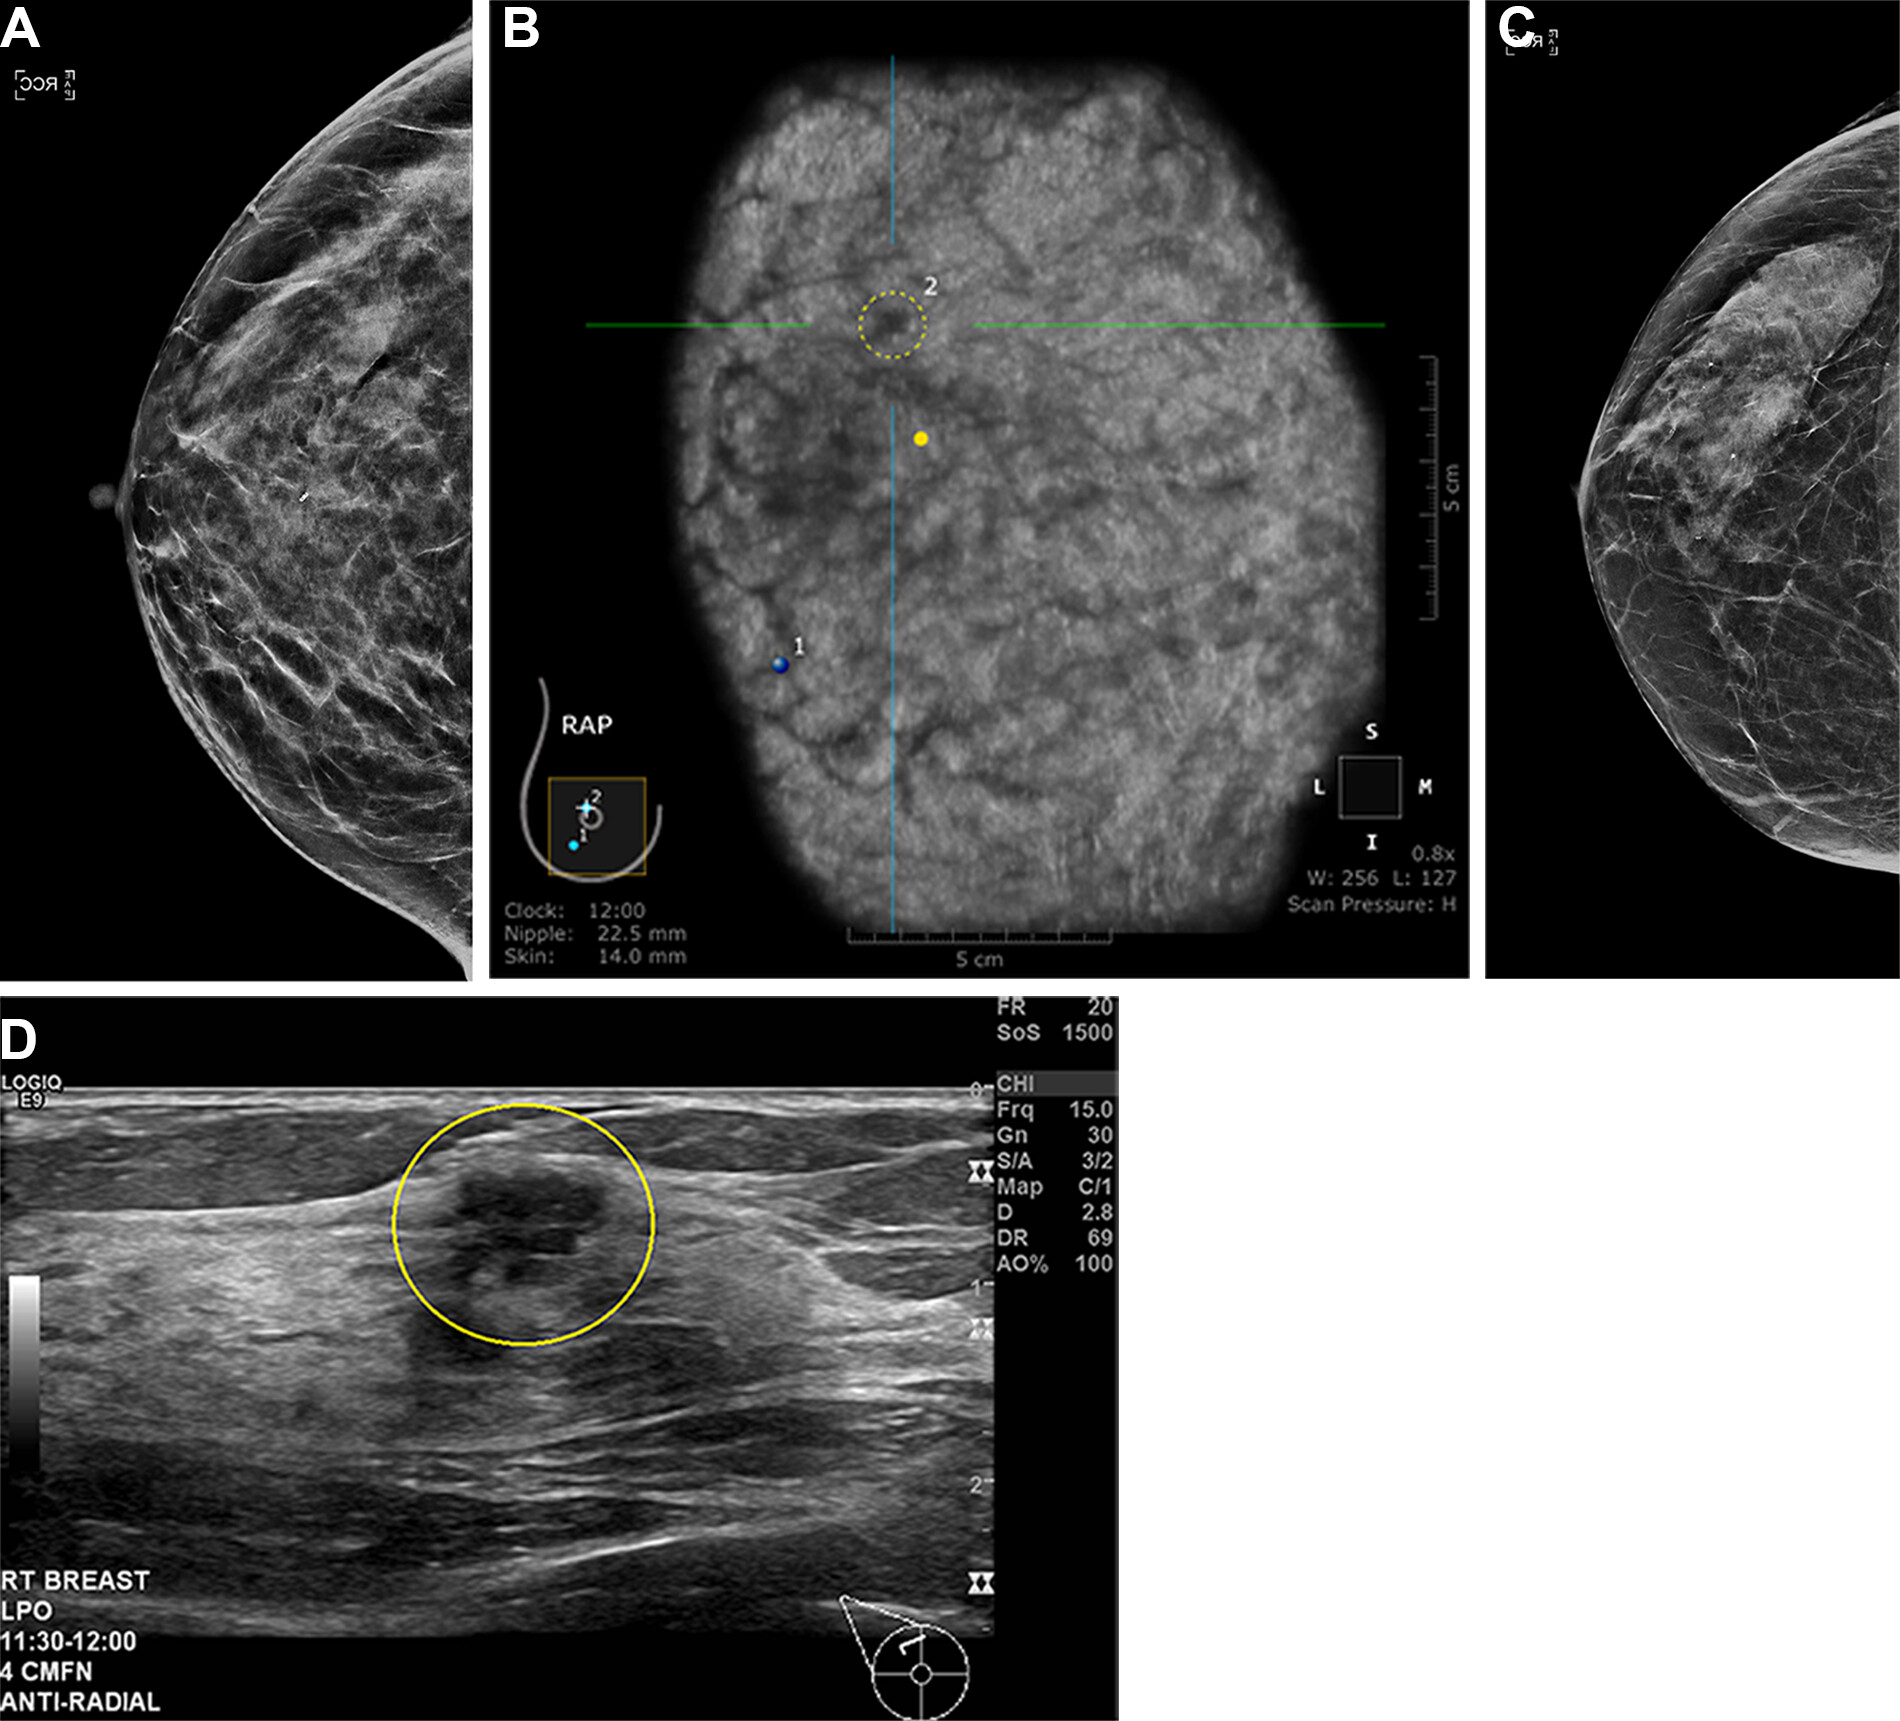

Images depict a 43-year-old woman with a malignant nonmass lesion that was diagnosed as microinvasive ductal carcinoma. (A) Transverse and (B) longitudinal ultrasound images show a hypoechoic nonmass lesion (solid arrows) with segmental distribution in the left breast. The lesion has associated calcifications (dashed arrows in A). (C) Longitudinal color Doppler ultrasound image shows high vascularity. (D) Magnified image in the mediolateral oblique view from screening mammography shows grouped calcifications (arrows), which are considered a mammographic correlate of the ultrasound-detected nonmass lesion (A radiopaque marker attached to the skin is visible in the image because the mammographic exam was performed after screening breast ultrasound). Ultrasound-guided core needle biopsy and pathologic examination revealed ductal carcinoma in situ, but the lesion was upgraded to microinvasive ductal carcinoma at subsequent surgery (2.5-cm ductal carcinoma in situ, histologic grade II, estrogen receptor-positive, progesterone receptor-positive, human epidermal growth factor receptor type 2-negative).RSNA